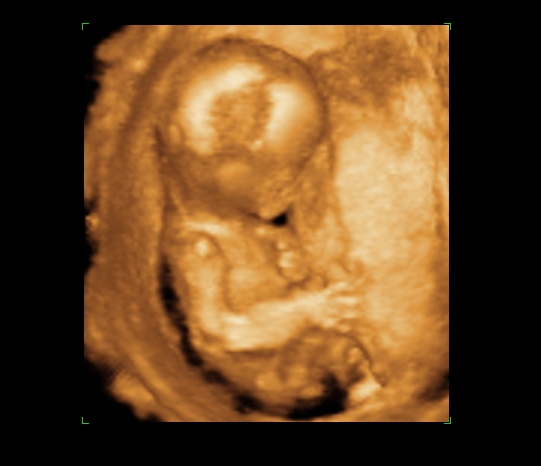

Csak gyors képek, mert pakolunk, a holnap meg rémes lesz, mert férjemnek még be kell mennie dolgozni, mielőtt indulunk :?

Lusta, kicsit kisebb a koránál, de gyönyörű, és lehet, hogy lány, de igazából nem lehetett látni, Annyira édes, inkább aludt volna :D